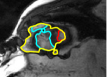

V-D Multiple Region Segmentation: Full Heart Segmentation

We now demonstrate our approach in performing challenging full heart segmentation: segmentation of the ventricles and epicardium all in one shot. Both the RV and epicardium are especially challenging as the contrast of the RV and background is subtle in comparison to the LV, and the myocardium wall near parts of the RV is very thin. We are not aware of another interactive method that is able to segment all structures, and so we compare to Medviso even though the method is not specifically tailored to the myocardium, but the method is generic and is able to propagate a segmentation. Further, Medviso does not segment multiple regions all at once and thus we perform separate segmentation of the LV, RV and epicardium. Since ground truth is not available for the outer wall of the myocardium in any standard dataset that we aware of, we show visual comparison.

Figure 10 shows the slice-wise results of our method and Medviso on a full 3D cardiac MRI sequence for a full cardiac cycle. Results indicate that our method is more accurate in capturing the shape of the ventricles and epicardium, and our method is especially more promising on the RV and epicardium. Figure 11 shows visualization of the results in 3D, and that our method more accurately resembles the structure of the heart.